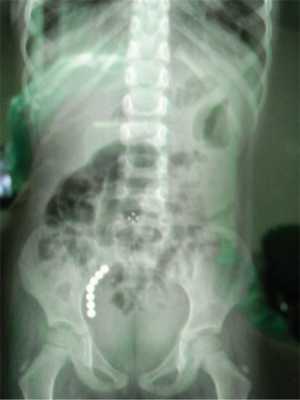

3. Больная Ф., 2 лет 3 мес. Поступила в приемный покой в связи с проглатыванием неизвестного количества магнитов круглой формы давностью, со слов матери, около 2 сут. При осмотре жалобы и беспокойство у ребенка отсутствовали, живот при пальпации мягкий, безболезненный во всех отделах. На обзорной рентгенограмме брюшной полости визуализируется цепочка округлых рентгеноконтрастных теней (75 штук) в проекции желудка и кишечника (рис. 2, а). Рис. 2. Больной Ф., 2 лет 3 мес. На рентгенографии брюшной полости визуализируется цепочка магнитов в проекции желудка; б — цепочка извлеченных из желудка магнитов в количестве 79 штук. Выполнена ФЭГДС, извлечена часть МИТ. Для удаления оставшейся цепочки магнитов, фиксированных магнитным полем через стенки желудка и двенадцатиперстной кишки, выполнена верхнесрединная лапаротомия: в рану выведен желудок, в котором пальпировались объекты, методом гастротомии удалено 78 магнитных шариков (см. рис. 2, б). Наложен двухрядный шов на стенку желудка. Рентгенологический контроль брюшной полости: МИТ отсутствуют. Послеоперационный период протекал гладко, выписана через 13 сут.

5. Больная М., 4 лет. Поступила в порядке скорой помощи с жалобами на боли в животе в течение 25 ч, повторяющуюся рвоту. При осмотре живот мягкий, болезненный в эпигастрии и правой подвздошной области, симптомы раздражения брюшины отрицательные. При УЗИ брюшной полости червеобразный отросток диаметром 6 мм, не изменен, но определялся конгломерат из петель кишечника, который не изменял своей формы и размера при полипозиционном обследовании, и не имел изменений кишечной стенки. Перистальтика кишечника отсутствовала. На рентгенограмме брюшной полости в проекции малого таза справа определяются контрастные тени в виде цепочки из 7 шариков диаметром 0,47 см (рис. 4, а). Локусы рентгенологической и ультразвуковой навигации МИТ кишечника совпадали. После предоперационной подготовки выполнено оперативное вмешательство (параректальный срединный разрез справа): при вскрытии брюшины серозный прозрачный выпот в объеме до 100 мл, при ревизии кишечника найдены два перфорационных отверстия (купол илеоцекального угла и основание червеобразного отростка) с наличием в их просвете МИТ (рис. 4, б) и третье перфорационное отверстие на тонкой кишке (расстояние до 50 см от илеоцекального угла), покрытое фибрином и с истечением кишечного содержимого (рис. 4, в). Из перфорационного отверстия на основании червеобразного отростка удалено 7 МИТ. Выполнена аппендэктомия, перфорации ушиты двухрядными швами, брюшная полость дренирована. Рентгенологический контроль брюшной полости: МИТ нет. Послеоперационный период гладкий, выписана в удовлетворительном состоянии через 16 сут.

Рис. 4. Больной М., 4 лет. а — на рентгенографии брюшной полости определяется цепочка из 7 МИТ в проекции кишечника; б — обнаружена перфорация на основании червеобразного отростка с наличием в просвете круглого магнита (указано стрелкой); в — перфорационное отверстие на тонкой кишке с истечением кишечного содержимого.

Рис. 4. (окончание) Больной М., 4 лет. а — на рентгенографии брюшной полости определяется цепочка из 7 МИТ в проекции кишечника; б — обнаружена перфорация на основании червеобразного отростка с наличием в просвете круглого магнита (указано стрелкой); в — перфорационное отверстие на тонкой кишке с истечением кишечного содержимого.